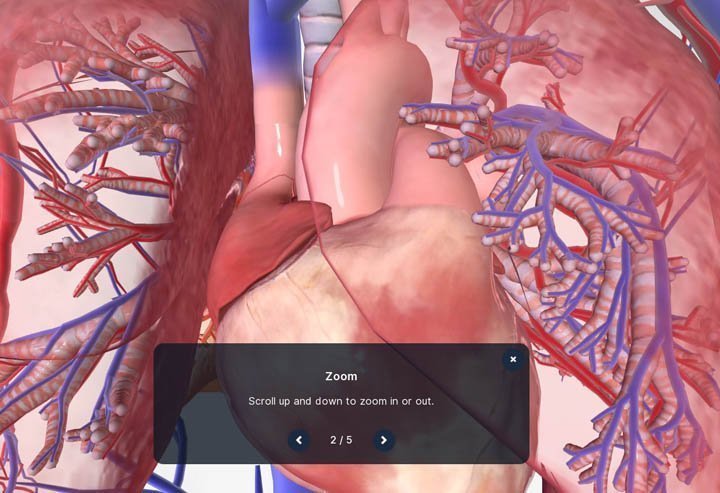

મોબાઇલ કે પીસીમાં human.biodigital.com સાઇટ પર, કોઈ પણ સિસ્ટમ ઓપન કર્યા પછી, માઉસથી ક્લિક-ડ્રગ કરીને કે આંગળીથી એનેટોમીનો વ્યૂઇંગ એંગલ બદલી શકાશે.

મોબાઇલ કે પીસીમાં human.biodigital.com સાઇટ પર, કોઈ પણ સિસ્ટમ ઓપન કર્યા પછી, માઉસથી ક્લિક-ડ્રગ કરીને કે આંગળીથી એનેટોમીનો વ્યૂઇંગ એંગલ બદલી શકાશે.

પીસીમાં માઉસ સ્ક્રોલ અપ કે ડાઉન કરીને ઝૂમ-ઇન કે આઉટ કરી શકાશે. મોબાઇલમાં આ જ કામ આંગળીથી કરી શકાશે.

પીસીમાં માઉસ સ્ક્રોલ અપ કે ડાઉન કરીને ઝૂમ-ઇન કે આઉટ કરી શકાશે. મોબાઇલમાં આ જ કામ આંગળીથી કરી શકાશે.

આખેઆખી એનેટોમીની જગ્યા બદલવી હોય, તો પીસીમાં શિફ્ટ કી પ્રેસ કરી, માઉસથી ડ્રેગ કરો. મોબાઇલમાં એક સાથે બે આંગળીથી ડ્રેગ કરીને એનેટોમીની પોઝિશન બદલી શકાશે.

આખેઆખી એનેટોમીની જગ્યા બદલવી હોય, તો પીસીમાં શિફ્ટ કી પ્રેસ કરી, માઉસથી ડ્રેગ કરો. મોબાઇલમાં એક સાથે બે આંગળીથી ડ્રેગ કરીને એનેટોમીની પોઝિશન બદલી શકાશે.

જુદા જુદા ભાગ ક્લિક કરીને માત્ર એ જ દેખાય એવું પણ કરી શકાશે. જેમ કે હૃદયના વિવિધ ભાગ પર ક્લિક કરી, તેના વિશે વધુ જાણી શકાશે. પીસીમાં દરેક ભાગ વિશે ઘણી વિસ્તૃત માહિતી મળશે.

જુદા જુદા ભાગ ક્લિક કરીને માત્ર એ જ દેખાય એવું પણ કરી શકાશે. જેમ કે હૃદયના વિવિધ ભાગ પર ક્લિક કરી, તેના વિશે વધુ જાણી શકાશે. પીસીમાં દરેક ભાગ વિશે ઘણી વિસ્તૃત માહિતી મળશે.

દરેક રચના જોતી વખતે એક ટૂલબાર ઓપન કરી શકાય છે. તેની મદદથી તમે ૩ડી વ્યૂઇંગ એક્સ્પિરીયન્સમાં વધુ કંટ્રોલ મેળવી શકશો.

દરેક રચના જોતી વખતે એક ટૂલબાર ઓપન કરી શકાય છે. તેની મદદથી તમે ૩ડી વ્યૂઇંગ એક્સ્પિરીયન્સમાં વધુ કંટ્રોલ મેળવી શકશો.